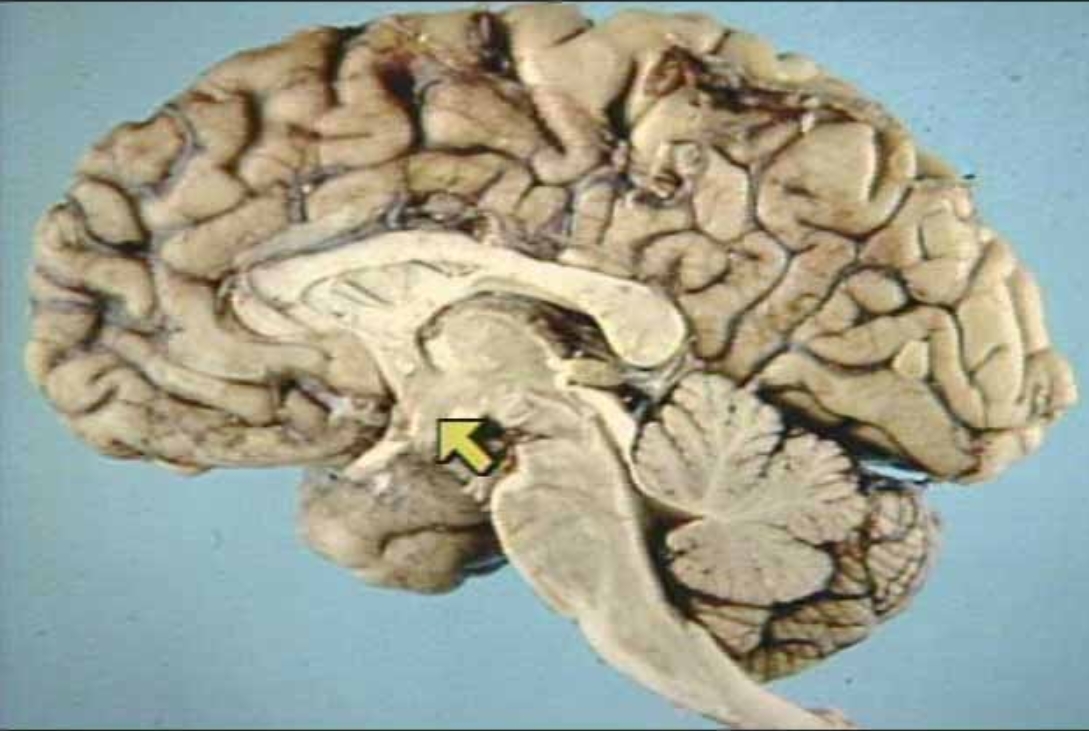

What is the arrow pointing at?

Corpus Callosum (Real Medial View of Brain)

Anterior Commissure (Real Medial View of Brain)